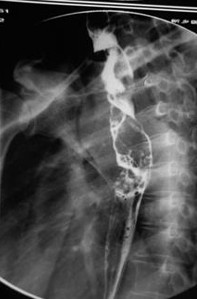

病例1 女,51歲,以“進(jìn)行性吞咽困難1年”為主訴于2007年2月19日入院。鋇餐造影、胃鏡示食管上段占位性病變,確診為食道鱗癌(圖1),拒絕手術(shù),行放療+今又生治療。食道鏡下瘤內(nèi)注射今又生,1×1012VP/次/周×6,…今又生治療病例---肉瘤